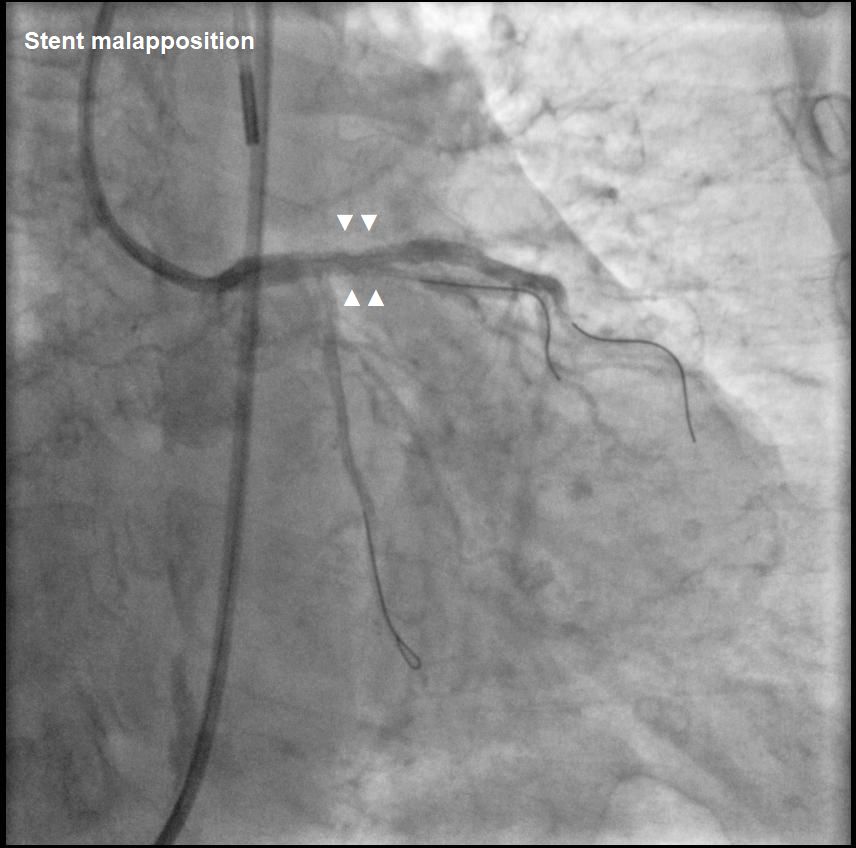

Guidewire entrapment during PCI is rare. In this case, the complication began with stent malapposition in the LAD, followed by post-dilatation that led to vessel perforation. During prolonged balloon inflation, the LCx wire was inadvertently pulled into the LAD, leading to guidewire entrapment when a covered stent was placed. Direct retrieval using a microcatheter was not possible, requiring surgery to cut the guidewire at the LM ostium, with the remaining LCx wire covered by a stent.